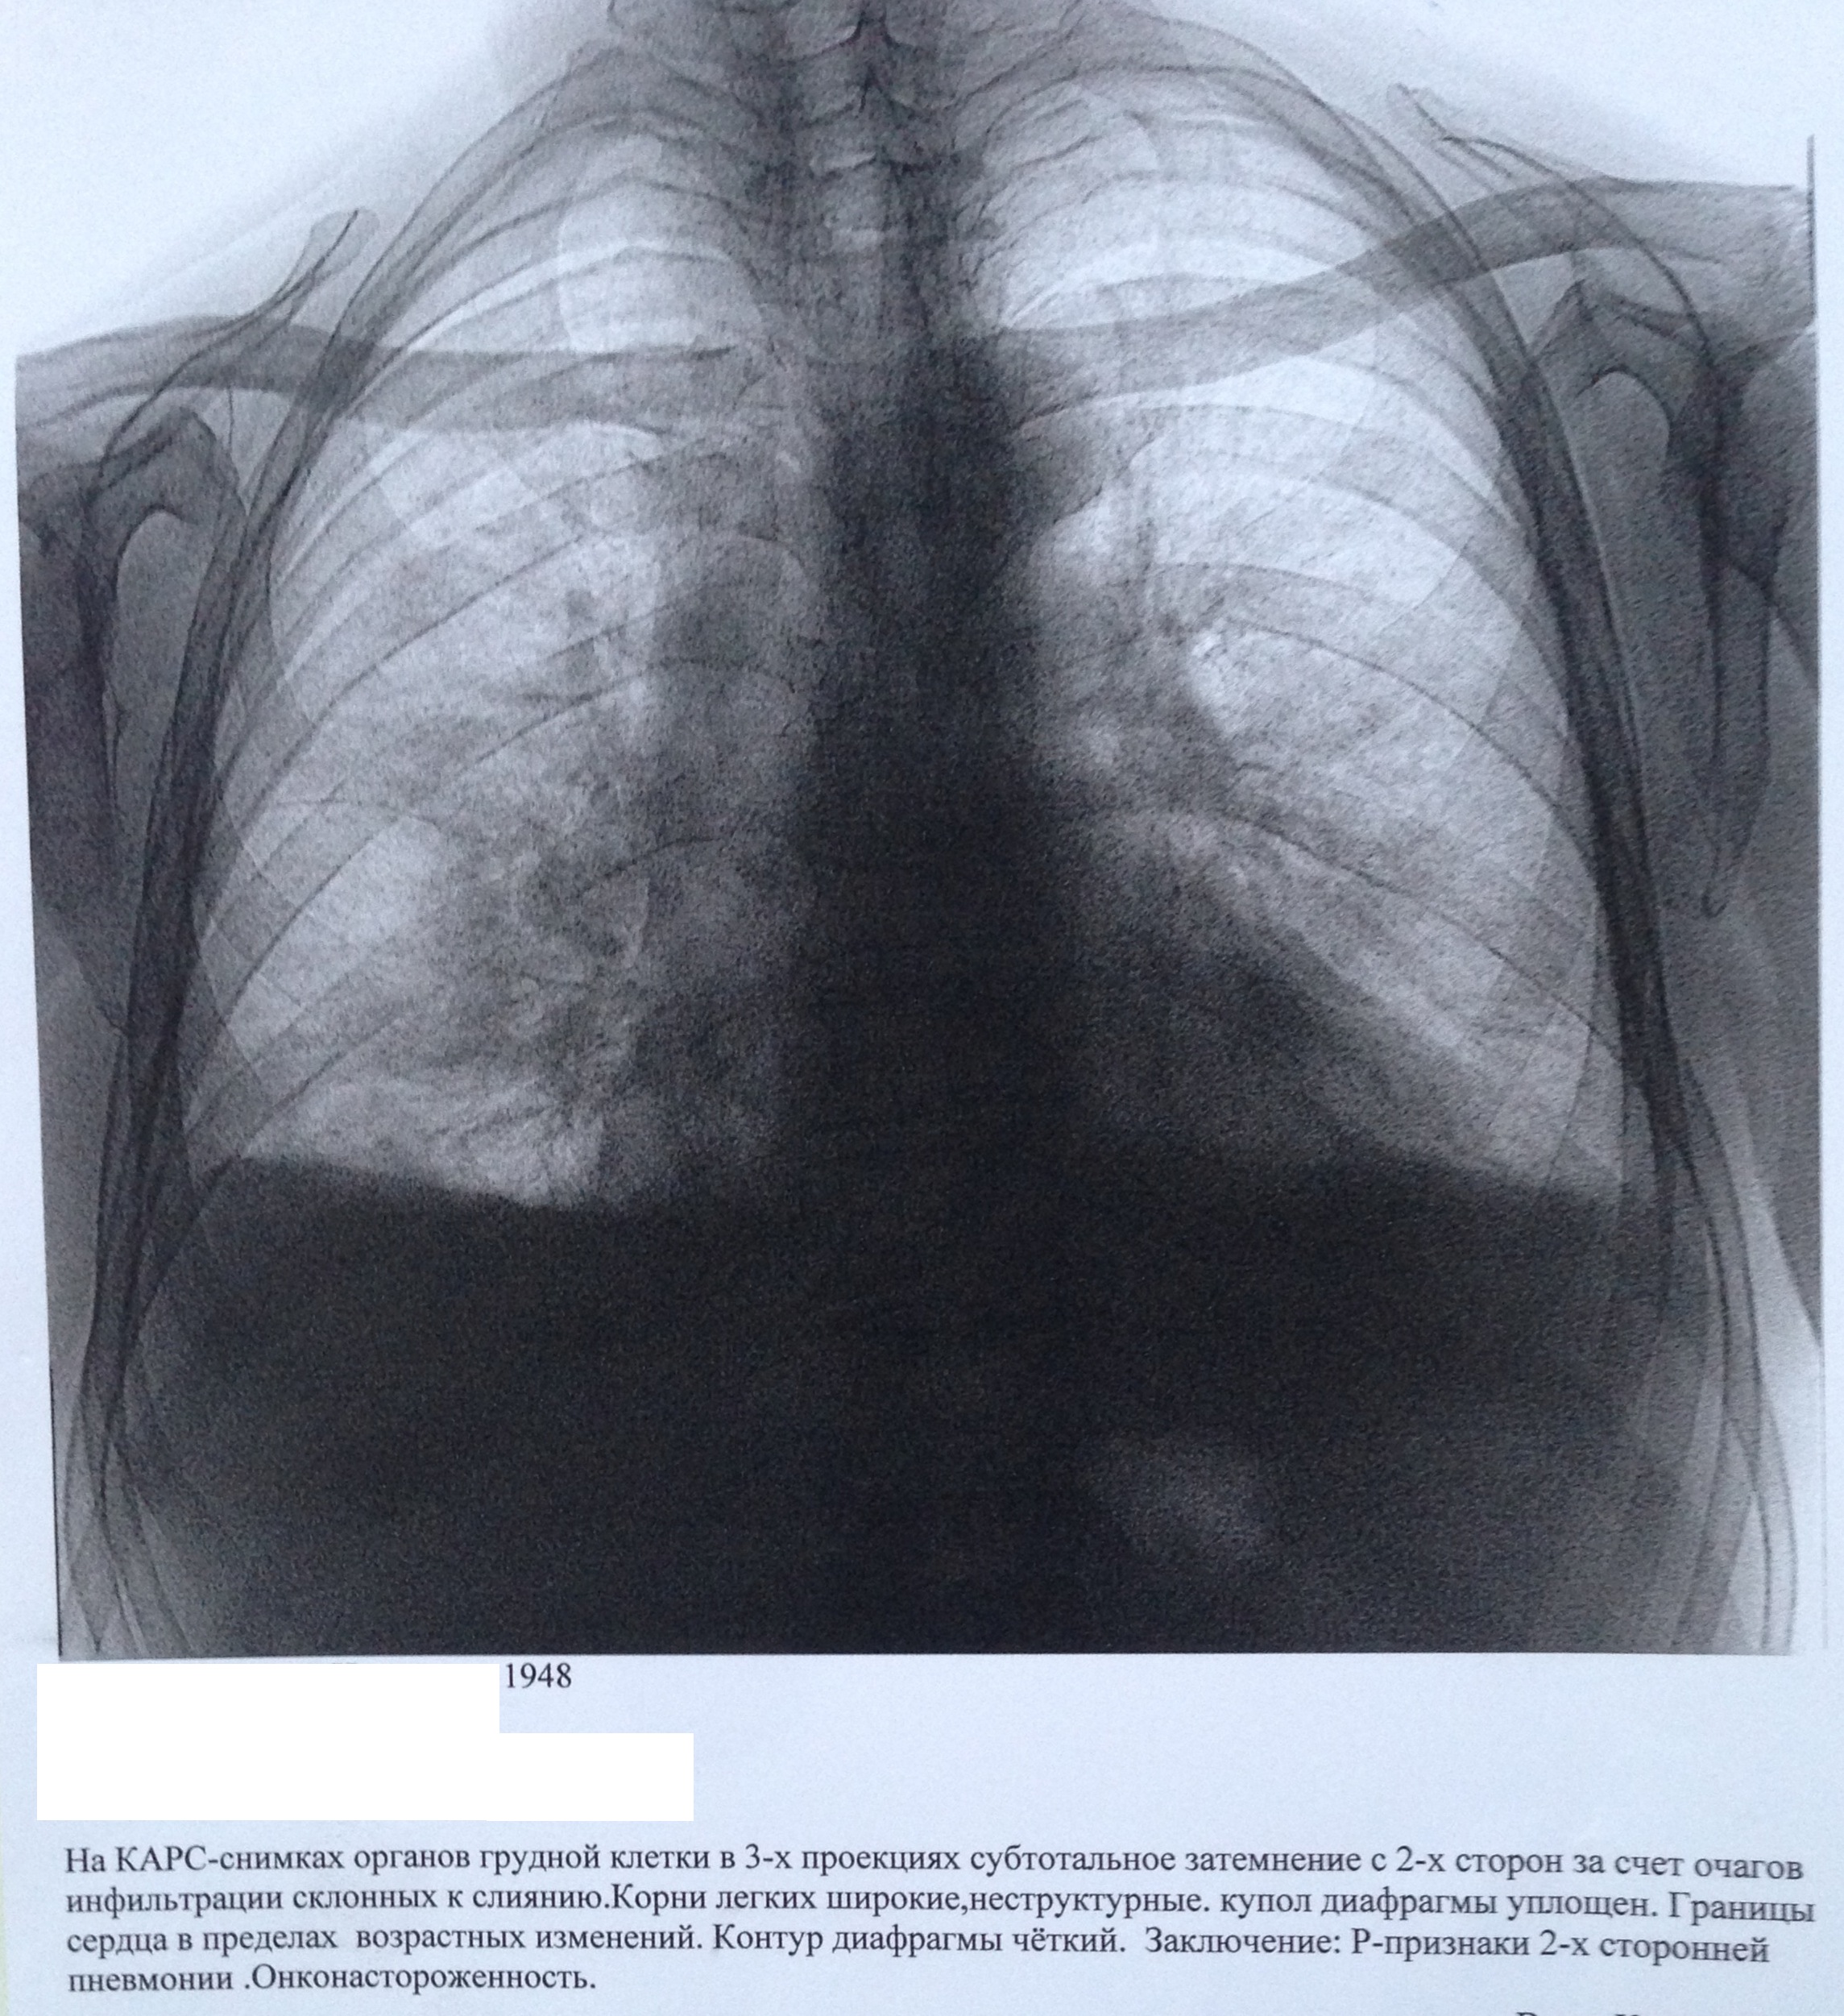

М 52.

На цифровых рентгенограммах органов грудной клетки в прямой и правой боковой проекциях определяются следующие изменения: в проекции сегментов S8, S9 справа на фоне массивных плевро-костальных и плевро-диафрагмальных спаек определяются отдельные участки консолидации легочной паренхимы по типу инфильтрации. Легочный рисунок усилен, деформирован диффузно. Корни малоструктурны, не расширены, тяжисты. Синусы слева свободный, справа запаян.Тень сердца не расширена. КТИ-0,47 Дуга аорты склерозирована.

Заключение: Р - признаки правосторонней, нижнедолевой, бисегментарной (S8-9) пневмонии на фоне массивных фиброзных изменений.